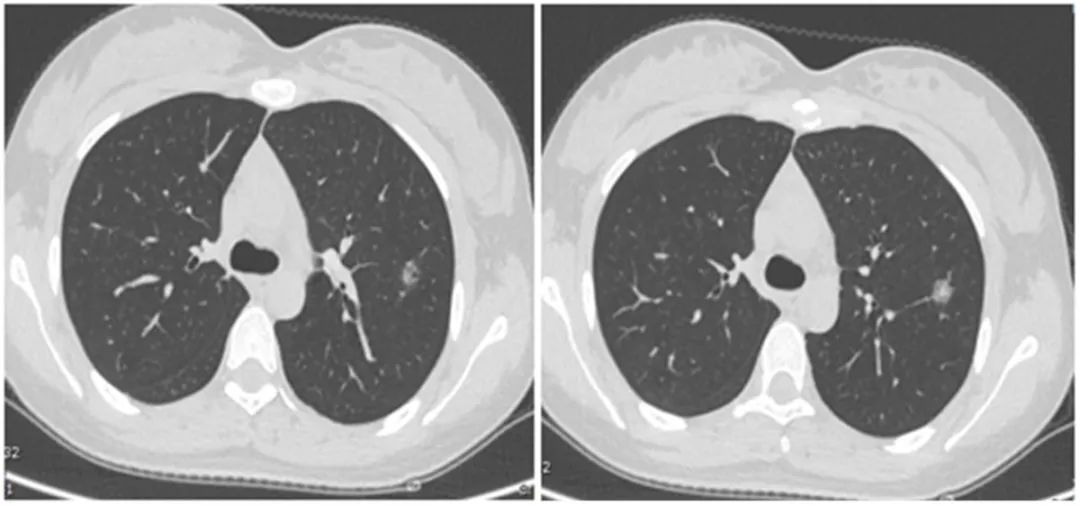

想知道肺手术中最重要的报告都告诉你什么了么?...

想知道肺手术中最重要的报告都告诉你什么了么?...